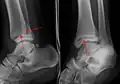

Description de cette image, également commentée ci-après

Radiographie antéropostérieure d'une fracture des deux côtés de la cheville avec luxation.

(1) fibula et malléolaire latéral (pointe de flèche),

(2) tibia et malléole médiale (flèche).